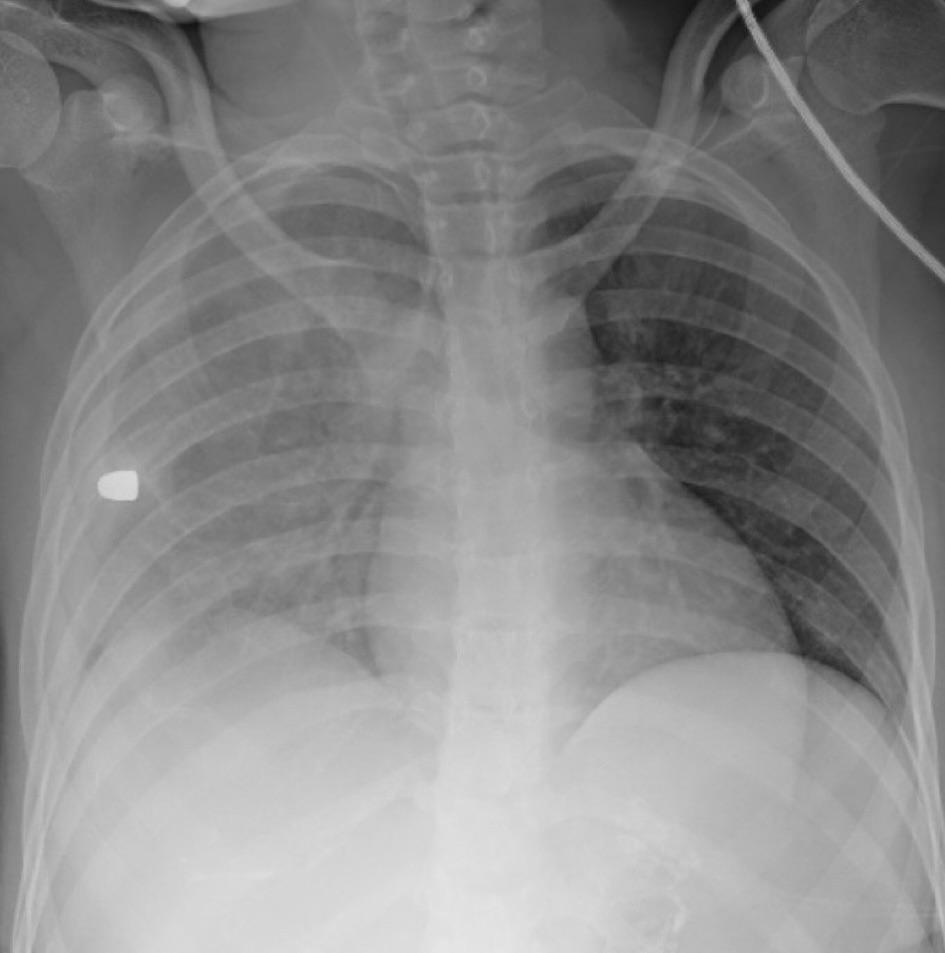

Chest x-ray of a young girl suffering from the leading cause of death in American children. Hint: it's not a book about a penguin having two dads, or a textbook talking about Rosa Parks. #ItsTheGuns #EndGunViolence #NoMoreThoughtsAndPrayers

Chest x-ray of a young girl suffering from the leading cause of death in American children.

Hint: it's not a book about a penguin having two dads, or a textbook talking about Rosa Parks.

#ItsTheGuns #EndGunViolence #NoMoreThoughtsAndPrayers